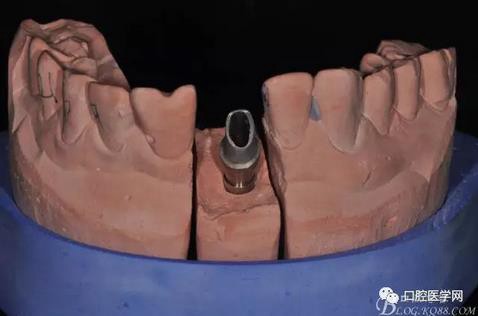

圖16 修復(fù)基臺模型頜面照

圖17 烤瓷冠唇側(cè)照